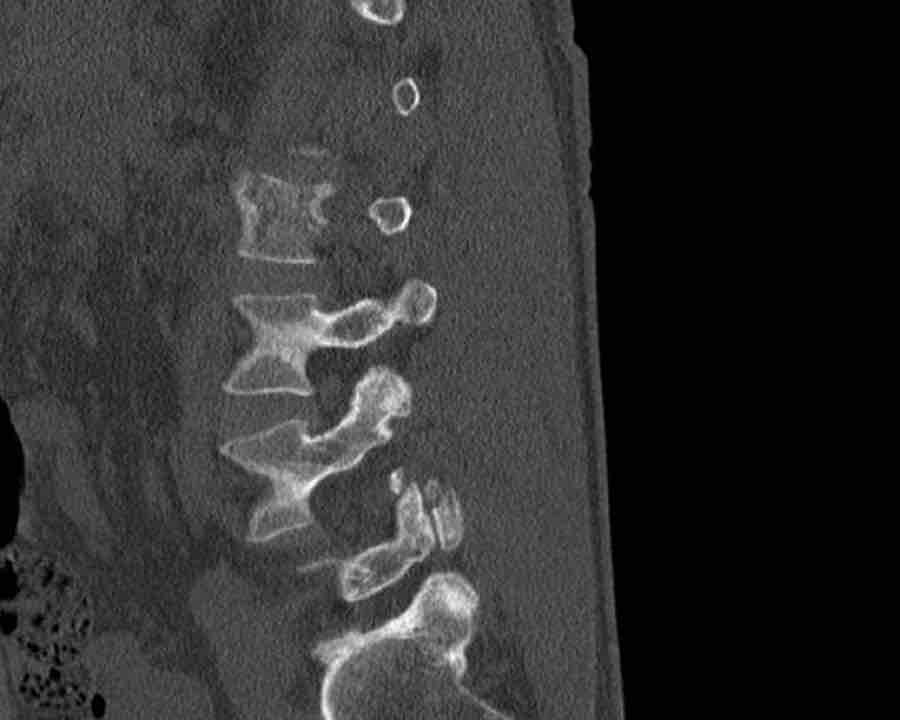

Scroll through the images

Findings:

- Perched facet joints (yellow curved arrows), so think of C injury.

- Posterior displacement of the vertebral bodies in the midline.

- Secondary A4 injury of the vertebral body.

Conclusion

Type C + A4 injury